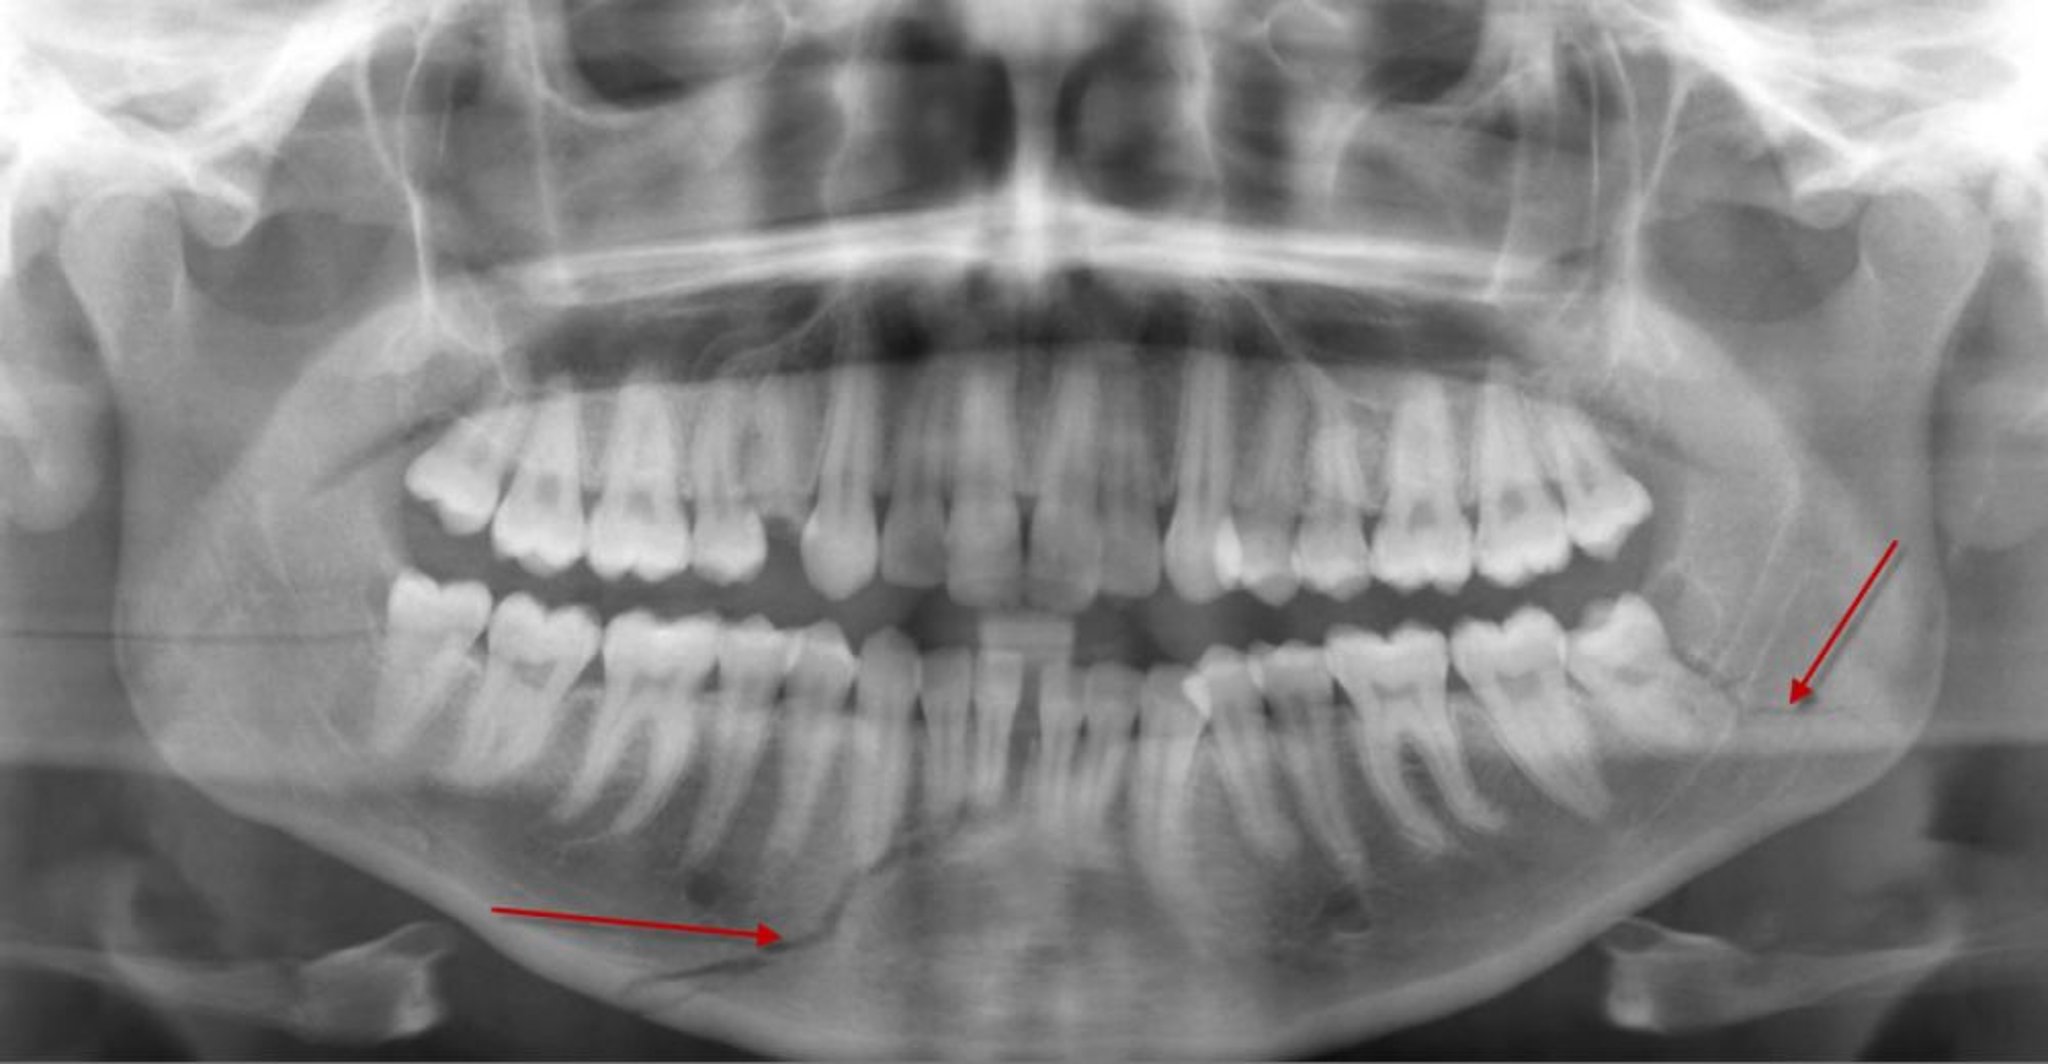

Перелом тіла нижньої щелепи

На цій панорамній рентгенограмі видно просвітління (стрілка знизу) в тілі нижньої щелепи, яке відповідає перелому, що досягає коренів деяких нижніх передніх зубів. Також спостерігається перелом кута нижньої щелепи зліва (стрілка).